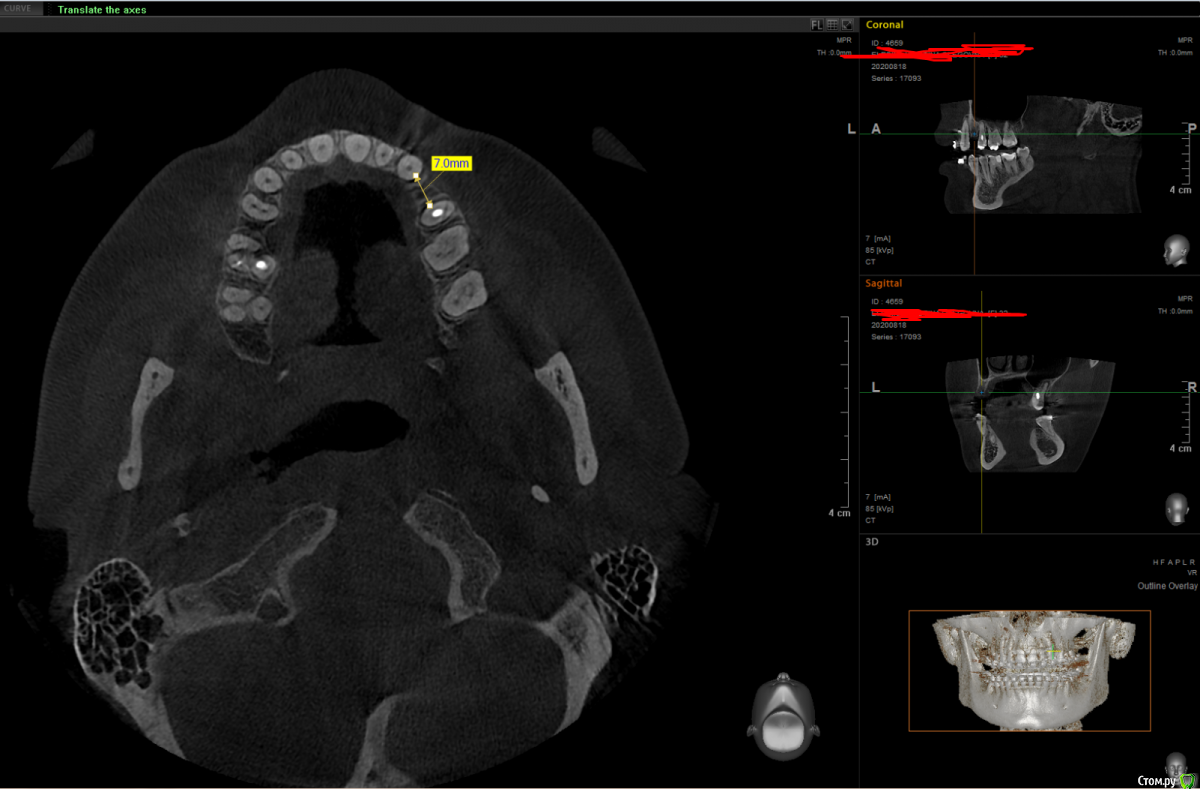

It'sGeorgy Опубликовано 19 ноября, 2020 Поделиться Опубликовано 19 ноября, 2020 Здравствуйте.Вот такая ситуация:Ставить планирую по шаблону с направляющей фрезой из Пикассо. Дополнительно ССТ с неба. Не могу определиться с имплантатом:Straumann BLT 2.9x10 или Straumann BL 3.3x10Производитель не рекомендует 2.9 на премоляры, но тут и размер коронки меньше, чем у стандартного премоляра. С другой стороны, жевательным зубом он быть от этого не перестает.Что посоветуете? Ссылка на комментарий

It'sGeorgy Опубликовано 19 ноября, 2020 Автор Поделиться Опубликовано 19 ноября, 2020 Ширина кости, в первую очередь. После установки диаметра 3.3мм останется по 1.3мм вестибулярно и орально. На мой взгляд, это очень близко к минимальной допустимой ширине стенок. Собственно, из этого и появились сомнения: может пожертвовать 0.4 титана, поставив диаметр 2.9, и получить лишние 0.4 кости. Опять же, небольшой размер коронки на это так же подталкивает. Вы бы поставили 3.3? Ссылка на комментарий

Bier Опубликовано 19 ноября, 2020 Поделиться Опубликовано 19 ноября, 2020 показания для 3.3 2 Ссылка на комментарий

red_butler Опубликовано 20 ноября, 2020 Поделиться Опубликовано 20 ноября, 2020 Мне кажется здесь рано имплантировать, мезиодистальное настояние мало, пусть ортодонт продолжит работу. А по кости конечно 3,3 2 Ссылка на комментарий

Nazim_NV86 Опубликовано 22 ноября, 2020 Поделиться Опубликовано 22 ноября, 2020 (изменено) Здравствуйте.Вот такая ситуация:1.png2.png3.pngСтавить планирую по шаблону с направляющей фрезой из Пикассо. Дополнительно ССТ с неба. Не могу определиться с имплантатом:Straumann BLT 2.9x10 или Straumann BL 3.3x10Производитель не рекомендует 2.9 на премоляры, но тут и размер коронки меньше, чем у стандартного премоляра. С другой стороны, жевательным зубом он быть от этого не перестает.Что посоветуете?Смотрите не на толщину кости, а на свои возможности. Если бы апроксимально место позволяло, я бы и 4.1 пристроил. Если под рукой есть диск или пьезо + экспандеры, то сделать +1-1.5мм вестибулярно вообще не проблема на ВЧ. Изменено 22 ноября, 2020 пользователем Nazim_NV86 1 Ссылка на комментарий